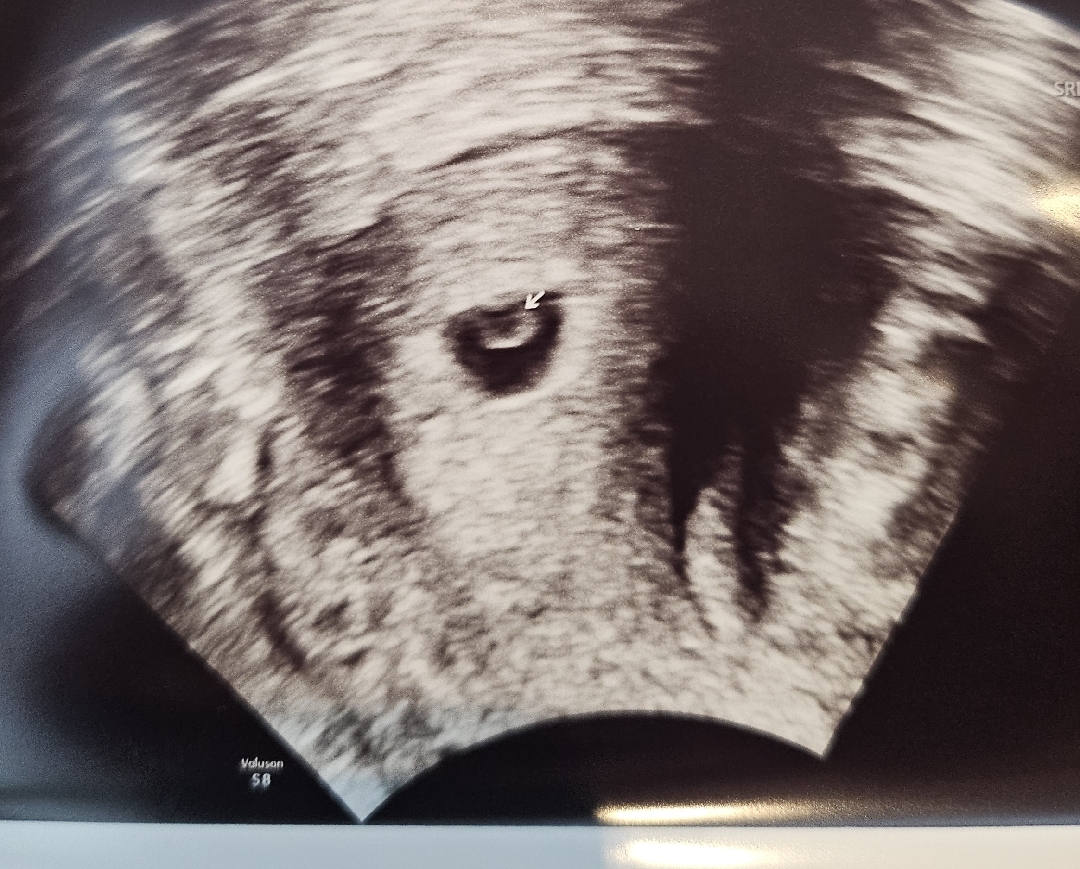

오늘 드디어 제대로 아기집 확인!

저번주 목요일에는 너무 작아서 아기집 추정 ㅋㅋㅋ 소리듣고 "저 점이요...?" 하고왔는데 오늘 정확히 확인하고왔어요! 난황도 좋다고하는데 얼마나 안심되던지ㅠㅠ 다들 배동이니 한창 불안하시겠지만 같이 이겨내봐요!